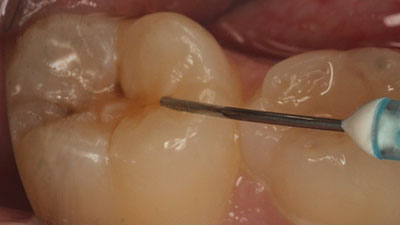

Surface Treatments of Non-Cavitated Proximal Lesions

Berg-Fig-2-thumbnail alternate text for this image

Introduction Most restorative dental treatment is because of dental caries, the most-prevalent disease in humans. Unchecked dental caries infection causes dentinal spread (cavitation) and destruction of tooth surfaces. Although we have been well trained as dental clinicians to diagnose caries lesions as early as possible, identifying the presence of early caries lesions proves to be … Read more